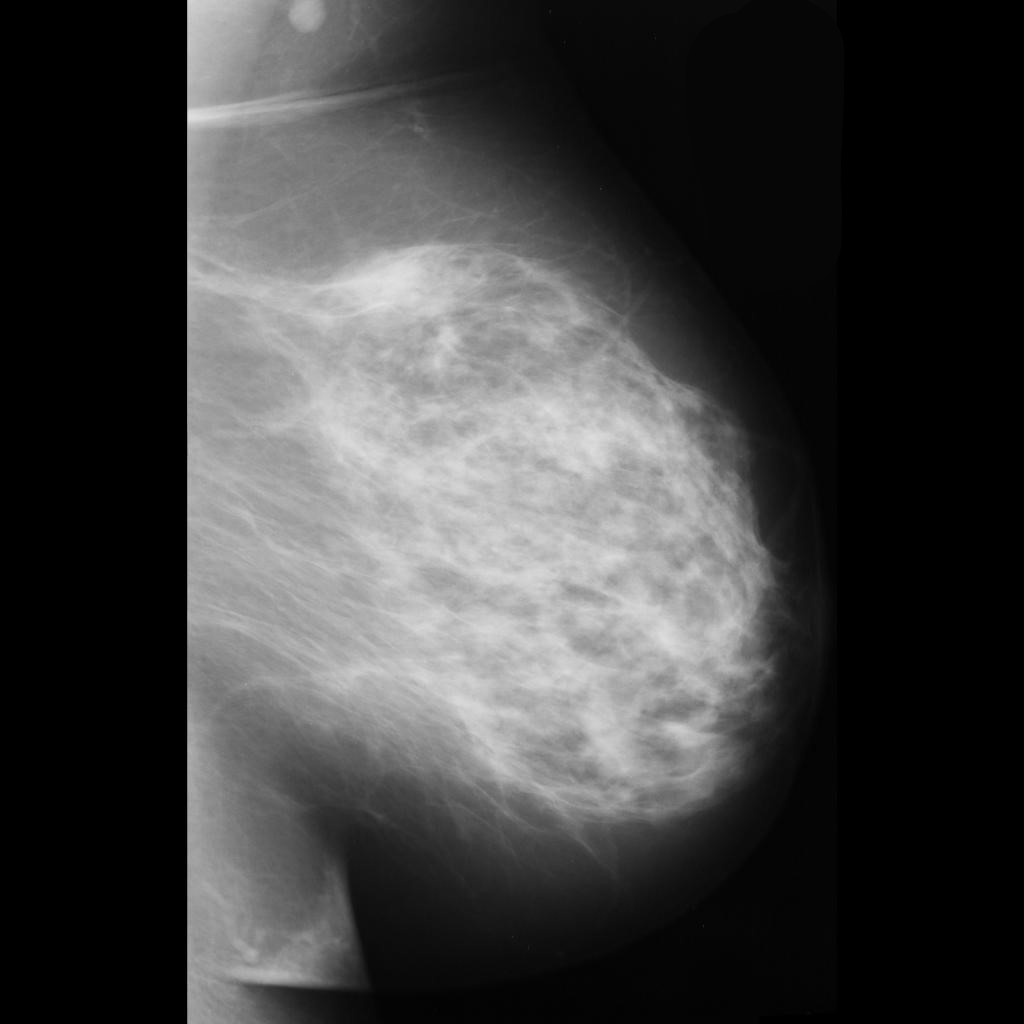

malignant